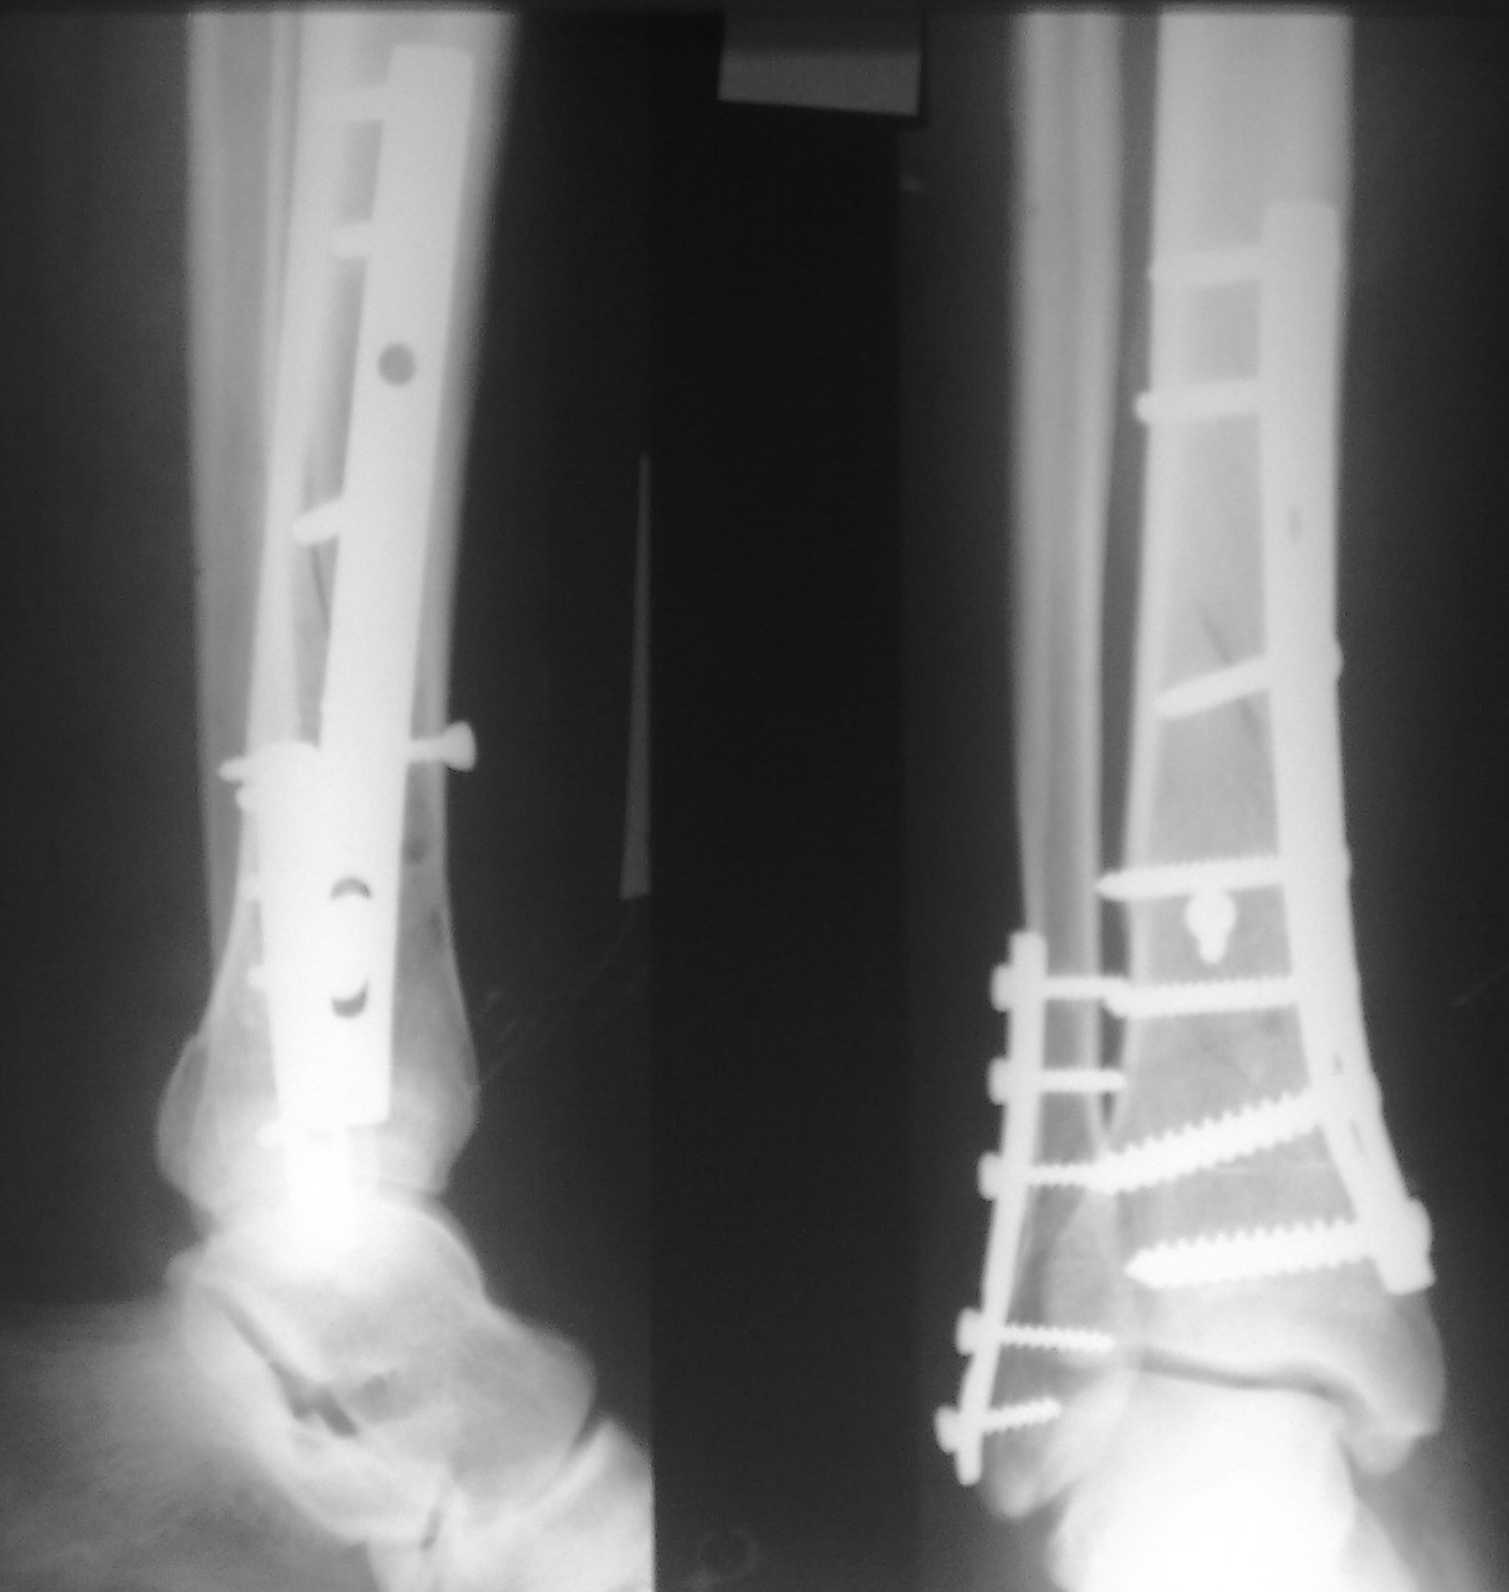

Re: Необходим ли МОС обеих костей голени?

послал Юрий 06 Январь 2011, 21:15

Спасибо за советы. Выполнен МОС обоих костей голени